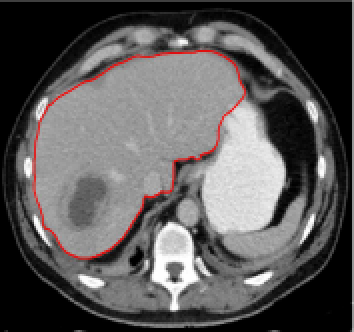

Four sets of test results are shown below. In Test 1 we compare models M1 – M6 to the proposed model M7 for two images which are hard to segment. The first is a CT scan from which we would like to segment the lower portion of the heart, the second is an MRI scan of a knee and we would like to segment the top of the Tibia. See Figure 9 for the test images and the marker sets used in the experiments. In Test 2 we will review the sensitivity of the proposed model to the main parameters. In Test 3 we will give several results achieved by the model using marker and anti-marker sets. In Test 4 we show the initialisation independence and marker independence of the Geodesic Model on real images.

In this test we give the segmentation results for models M1 – M7 for the two challenging test images shown in Figure 9. The marker and anti-marker sets used in the experiments are also shown in this figure. After extensive parameter tuning, the best final segmentation results for each of the models are shown in Figures 10 and 11. For M1 – M4 we obtain incorrect segmentations in both cases. In particular, the results of M2 and M4 are interesting as the former gives poor results for both images, and the latter gives a reasonable result for Test Image 1 and a poor result for Test Image 2. In the case of M2, the regularisation term includes the edge detector and the distance penalty term (see (4)). It is precisely this which permits the poor result in Figures 10(b) and 11(b) as the edge detector is zero along the contour and the fitting terms are satisfied there (both intensity and area constraints) – the distance term is not large enough to counteract the effect of these. In the case of M4, the distance term and edge detector are separated from the regulariser and are used to weight the Chan-Vese fitting terms (see (9)). The poor segmentation in Figure 11(b) is due to the Chan-Vese terms encouraging segmentation of bright objects (in this case), weighting enforces these terms at all edges in the image and near . In experiments, we find that M4 performs well when the object to segment is of approximately the highest or lowest intensity in the image, however when this is not the case, results tend to be poor. We see that, in both cases, models M5 and M6 give much improved results to M2 and M4 (obtained by incorporating the geodesic distance penalty into each). The proposed Geodesic Model M7 gives an accurate segmentation in both cases. It remains to compare M5, M6 and M7. We see that M5 is a non-convex model (and cannot be made convex [39]), therefore results are initialisation dependent. It also requires one more parameter than M6 and M7, and an accurate set to give a reasonable area constraint in (4). These limitations lead us to conclude M6 and M7 are better choices than M5. In the case of M6, it has the same number of parameters as M7 and gives good results. M6 can be viewed as the model M7 with weighted intensity fitting terms (compare (18) and (30)). Experimentally, we find that the same quality of segmentation result can be achieved with both models generally, however M6 is more parameter sensitive than M7. This can be seen in the parameter map in Figure 12 with M7 giving an accurate result for a wider range of parameters than M6. To show the improvement of M7 over previous models, we also give an image in Figure 13 which can be accurately segmented with M7 but the correct result is never achieved with M6 (or M3). Therefore we find that M7 outperforms all other models tested M1 – M6.

Test 3 – Further Results from the Geodesic Model M7. In this test we give some medical segmentation results obtained using the Geodesic Model M7. The results are shown in Figure 14. In the final two columns we use anti-markers to demonstrate how to overcome blurred edges and low contrast edges in an image. These are challenging and it is pleasing to see the correctly segmented results.

(i) (ii) (iii) (iv) (v)